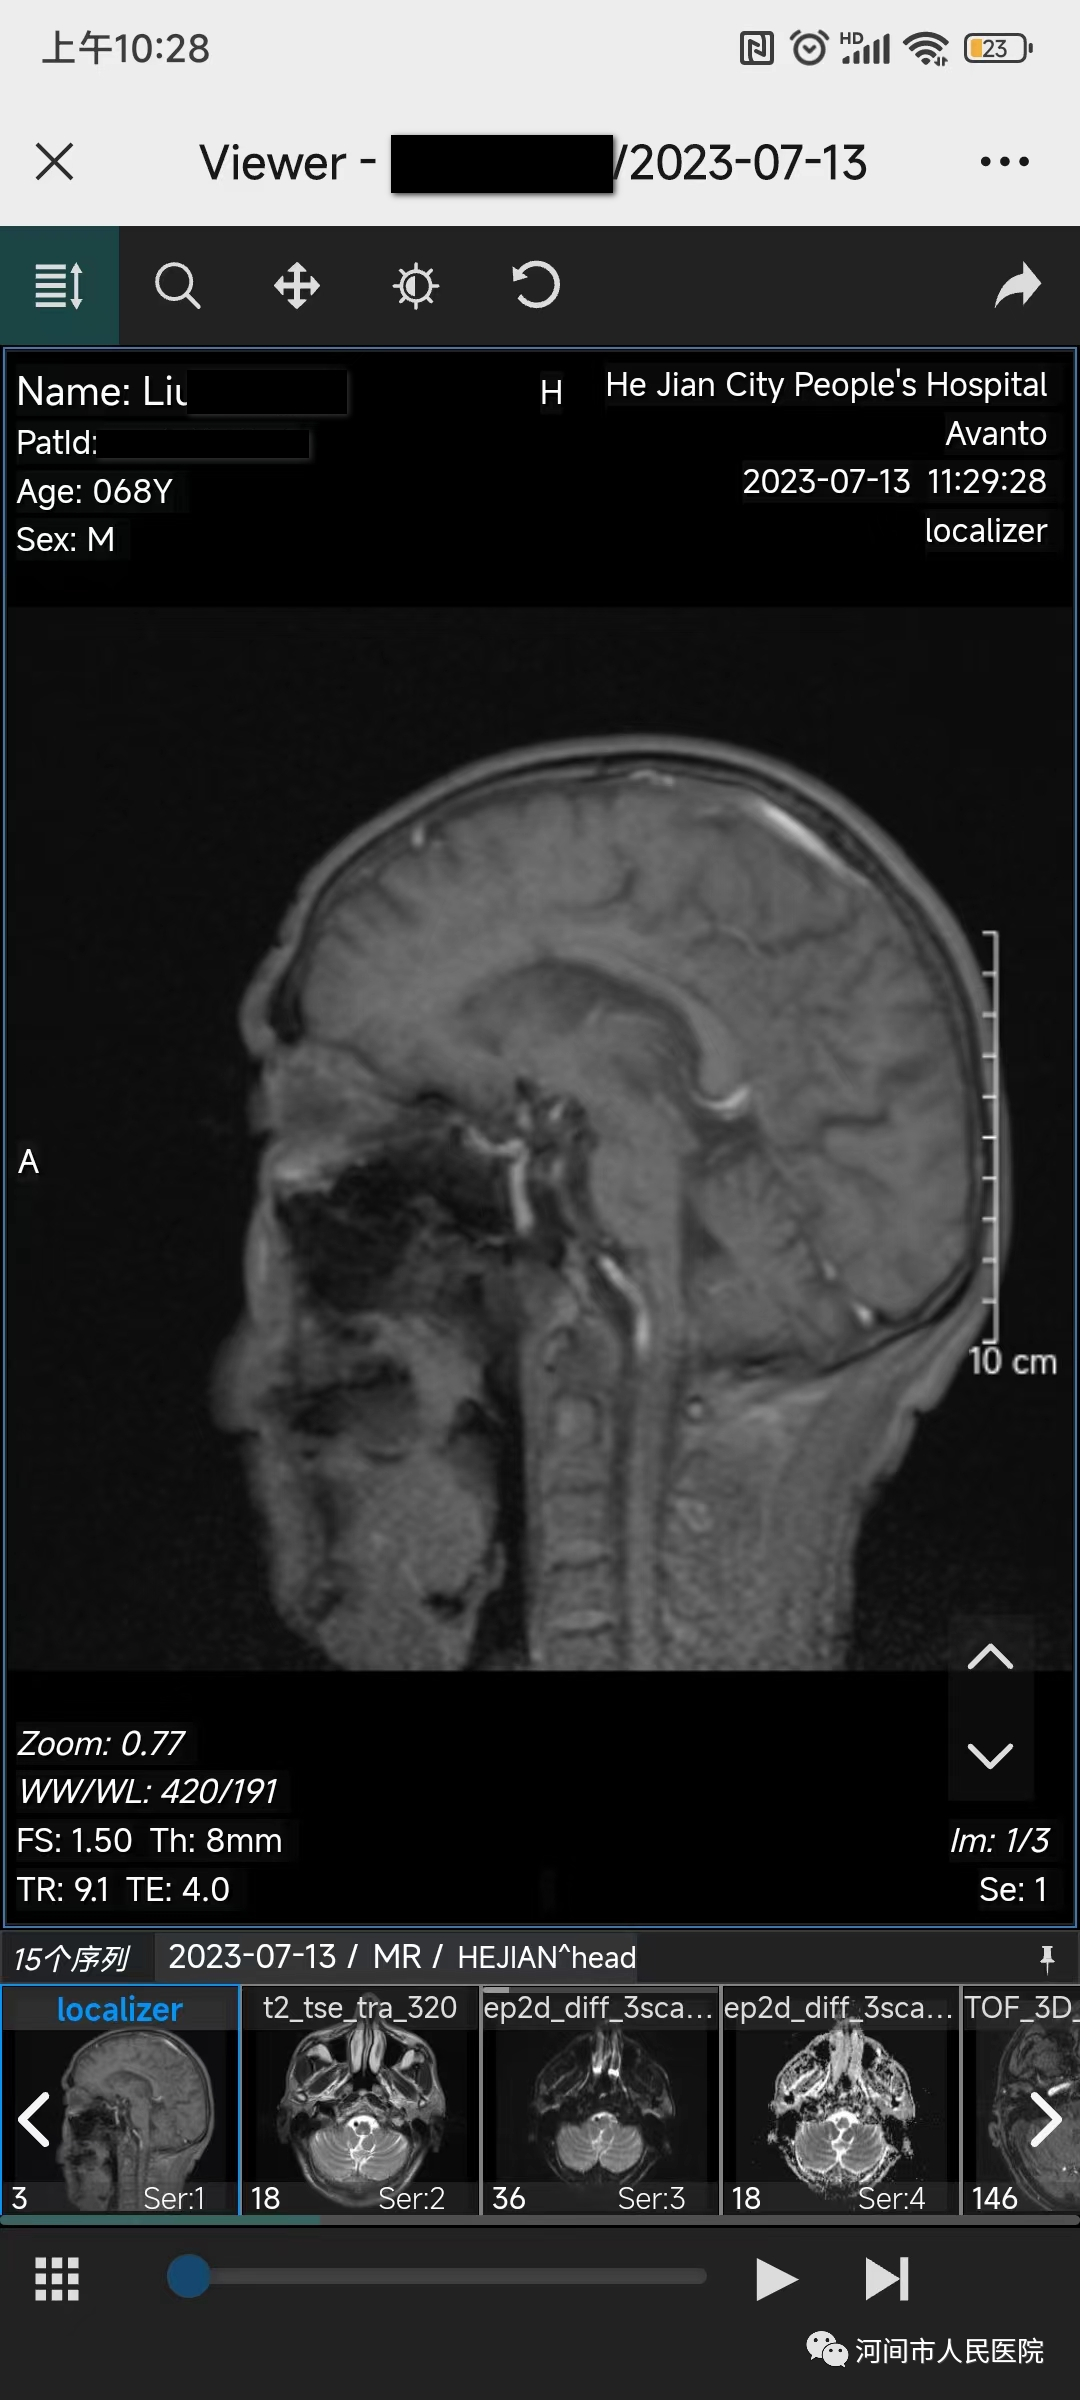

医院在开展影像检查时,将DICOM格式图片存储在影像云平台上,患者可通过扫描二维码随时在手机上进行调阅、下载影像(磁共振、CT、放射)检查结果。

1、就诊更便捷。患者在做完相应的影像学检查后,在手机上可随时查询影像检查结果,无需往返医院取片,减少患者往返医院次数。

2、诊断更精确。手机影像云可提供完整的原始影像数据,也可查询已上传到影像云平台所有历史影像数据,医生可分析对比前后检查的影像结果,做出更科学、更精确的诊断。

3、分享更方便。如需要远程会诊,可通过微信分享二维码,专家可查看原始影像,不需要长途奔波,更省时省钱。